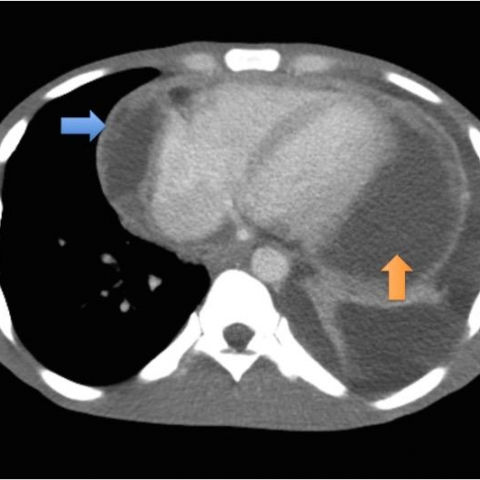

One of the most dreaded complications of tuberculosis is tuberculous pericarditis. The pericardium is usually involved via hematogenous route. Signs and symptoms of pericardial tuberculosis are often vague and difficult to discern. Common features are fever, diastolic sounds, fatigue, cough, and chest pain, Reference: https://www.ahajournals.org/doi/full/10.1161/circulationaha.105.543066 Image via: https://www.eurorad.org/case/13351